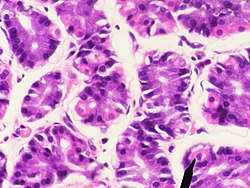

Das Epithel der Magenschleimhaut besteht nur aus einer Zellschicht aus hochprismatischen (höher als breit) Zellen (einschichtiges hochprismatisches Epithel). Die Zellen (Epitheliocyti superficiales gastris) sind durch sogenannte Tight Junctions fest untereinander verbunden. Im Epithel sind zahlreiche schleimproduzierende Nebenzellen eingestreut. Der Schleim dieser Zellen und der der Magendrüsen (s. u.) schützt das Epithel vor der im Magen produzierten Salzsäure.

Die Eigenschicht besteht aus Bindegewebe, Blutgefäßen, Lymphgefäßen, Zellen des Immunsystems (teilweise als Lymphfollikel) und Drüsen. Die Magendrüsen (Glandulae gastricae) münden in die Magengrübchen. Es handelt sich um schlauchförmige (tubuläre) Drüsen. Je nach Magenregion sind diese unterschiedlich ausgebildet und erfüllen auch unterschiedliche Funktionen. Man unterscheidet Kardia-, Fundus- und Pylorusdrüsen. Im Epithel der Magendrüsen sind neben exokrinen Zellen auch endokrin tätige Zellen integriert, die zum diffusen neuroendokrinen System (DNES) gehören.

Die Fundus- oder auch Eigendrüsen (Glandulae gastricae propriae) bilden den eigentlichen Magensaft. Sie erstrecken sich auf den Magenboden (Fundus) und -körper (Corpus ventriculi). Es sind gestreckte Schlauchdrüsen mit verschiedenen Zelltypen. Diese Schläuche werden in drei Abschnitte unterteilt:

Die Zellen des Isthmus bestehen zum Teil aus Epithelzellen. Sie bilden, wie das übrige Epithel, Schleim (Mucus) und Bicarbonat-Ionen, die als Basen eine Pufferwirkung gegenüber den freien Protonen haben. Dieser alkalische Schleim schützt das Epithel vor dem sauren Milieu des Magens. Weiter in der Tiefe befinden sich Stammzellen, die sich kontinuierlich teilen und die absterbenden Epithelzellen ersetzen.[1]

Im Drüsenhals kommen vor allem Neben- und Belegzellen vor. Im Hauptteil liegen die Hauptzellen und auch einige Belegzellen.

Die Nebenzellen (Mucocyti cervicales) sind iso- bis hochprismatisch und besitzen einen basalen Zellkern. Sie sezernieren ebenfalls alkalischen Schleim zum Schutz des Epithels.

Die Belegzellen (Exocrinocyti parietales, auch Parietalzellen) liegen zwischen den übrigen Zellen oder ihnen außen an. Sie sezernieren Protonen, die sich extrazellulär mit Chloridionen zu Salzsäure zusammenlagern, und den für die Cobalamin-Resorption (Vitamin B12) notwendigen intrinsischen Faktor. Die Zellen bilden intrazelluläre Sekretkanäle mit Mikrovilli. Diese Kanäle werden im aktiven Zustand der Zellen in die luminale (zum Magenraum gerichtete) Plasmamembran eingebaut und vergrößern so die Kontakt- und Abgabefläche. Hier befinden sich Protonen-Kalium-Pumpen, die Protonen im Austausch gegen Kaliumionen aus der Zelle transportieren. Belegzellen sind relativ groß und eosinophil (mit Eosin anfärbbar und daher rötlich).[1]

Die Hauptzellen (Exocrinocyti principales) im Hauptteil der Magendrüsen sind hochprismatisch mit einem basal liegenden Zellkern. Sie bilden Pepsinogene, die Vorstufen verschiedener Enzyme, die zusammengefasst als Pepsine bezeichnet werden (bei Wiederkäuern das Lab). Sie werden in sogenannten Zymogengranula in den Zellen zwischengespeichert. Hauptzellen sind durch den großen Anteil an rauem Endoplasmatischem Retikulum (rER) basophil (mit basophilen Farbstoffen anfärbbar, daher bläulich).[1]